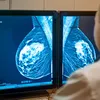

Het klopt. De IARC, de gespecialiseerde kankeronderzoekstak van de WHO, heeft bewerkt vlees ingedeeld in Groep 1: "kankerverwekkend voor de mens". In diezelfde groep vind je ook stoffen als tabaksrook en asbest.

Maar precies hier ontstaat de verwarring. Deze indeling zegt niets over hoe gevaarlijk iets is, maar alles over hoe zeker de wetenschap ervan is. Het bewijs dát bewerkt vlees de kans op kanker kan verhogen, is net zo ijzersterk als het bewijs voor roken. Concreet stelden de onderzoekers vast dat elke 50 gram bewerkt vlees die je dagelijks eet, de kans op darmkanker met circa 18% verhoogt.